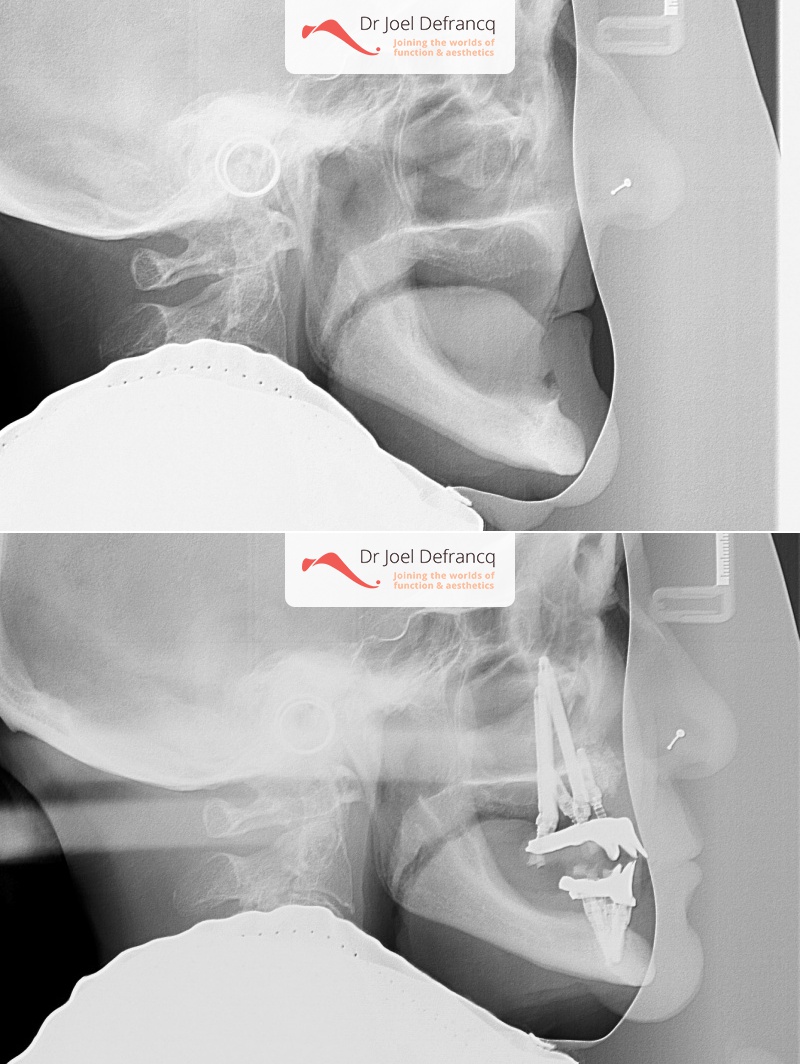

Behandeling tandheelkundige implantaten

- Vaste tanden op implantaten (bovenkaak)

- Vaste tanden op implantaten (onderkaak)

- Zygoma implantaten